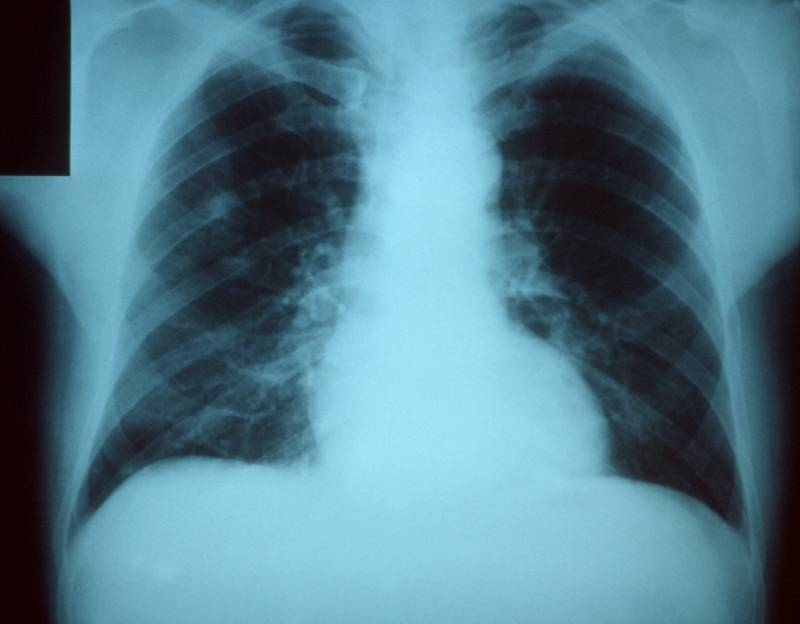

肺炎病人的胸部X光片

第二步:引发肺炎(lung inflammation)

流感病毒入侵人体,各种白细胞出动,它们在体内与流感病毒作战,炎症就产生了。炎症是身体对各种不适的免疫反应——不管是病毒,还是细菌,亦或是物理创伤。不过这种免疫反应目的都是一样的,都是为了治愈自身。这种情况下,皮肤和器官会有稍微的膨胀,以容纳所有涌入的新细胞,它们都在为修复我们的身体而苦苦奋战。虽说小型感染不足为虑,但是炎症过多却可能带来危险。

以肺部为例,肺部肿胀会导致氧气无法被输送到血管。氧气通常会穿过肺叶内无数非常薄的膜,当这些组织因免疫系统的作用而肿胀时,氧气就很难被输送到那些毛细血管。这会对肺组织造成一定程度的损伤。

由于病毒缺乏增殖所需的酶系统,无法自我复制,所以这一过程必须在人体细胞内进行。这意味着为了杀死病毒,免疫系统在某种程度上不得不破坏我们的身体,而这会使氧气输送变得更加困难。

死于流感的人中,大约有三分之一是直接死亡的。也就是说,他们死于病毒的影响(以及他们的身体试图对抗病毒所引发的结果)。呼吸衰竭——因为我们的肺不能获得足够的氧气——是最常见的死亡原因之一。它同时也是最快的死亡原因。由流感导致的直接死亡突如其来,通常在毫无预警的情况下几天内就会夺去患者的生命。

第四步:继发性感染,最有可能是肺感染(pneumonia)

但是,当我们的免疫系统在对抗病毒的重压下变得不堪重负时,这些细菌就会趁机倾巢而出,扩散到肺部并占据上风,这被称为继发性感染,当它发生在肺部时,我们称之为肺感染。与直接死亡不同,继发性肺感染作用得更慢一些。当人体在免疫系统的努力之下开始更为有效地对抗流感病毒之后,我们通常会在几天内感觉身体状况有所好转。

然后,突然,情况就会急转直下。因为这些有害的细菌已经在这几天里尽占先机,此时此刻它们已然在我们的肺里迅速繁殖起来,而我们的免疫系统虽然已经筋疲力竭,却仍然不得不全力以赴。

如果我们在身体每况愈下时还没有去医院检查,我们死于感染的可能性会大大上升。如果你及时就医,那抗生素会助你一臂之力,但这也不能保证你会安然无恙。因为有时细菌已经扩散得非常快,抗生素都没有办法迅速地杀死它们。即使你被治疗痊愈,器官也可能会不可逆转地受到损害。